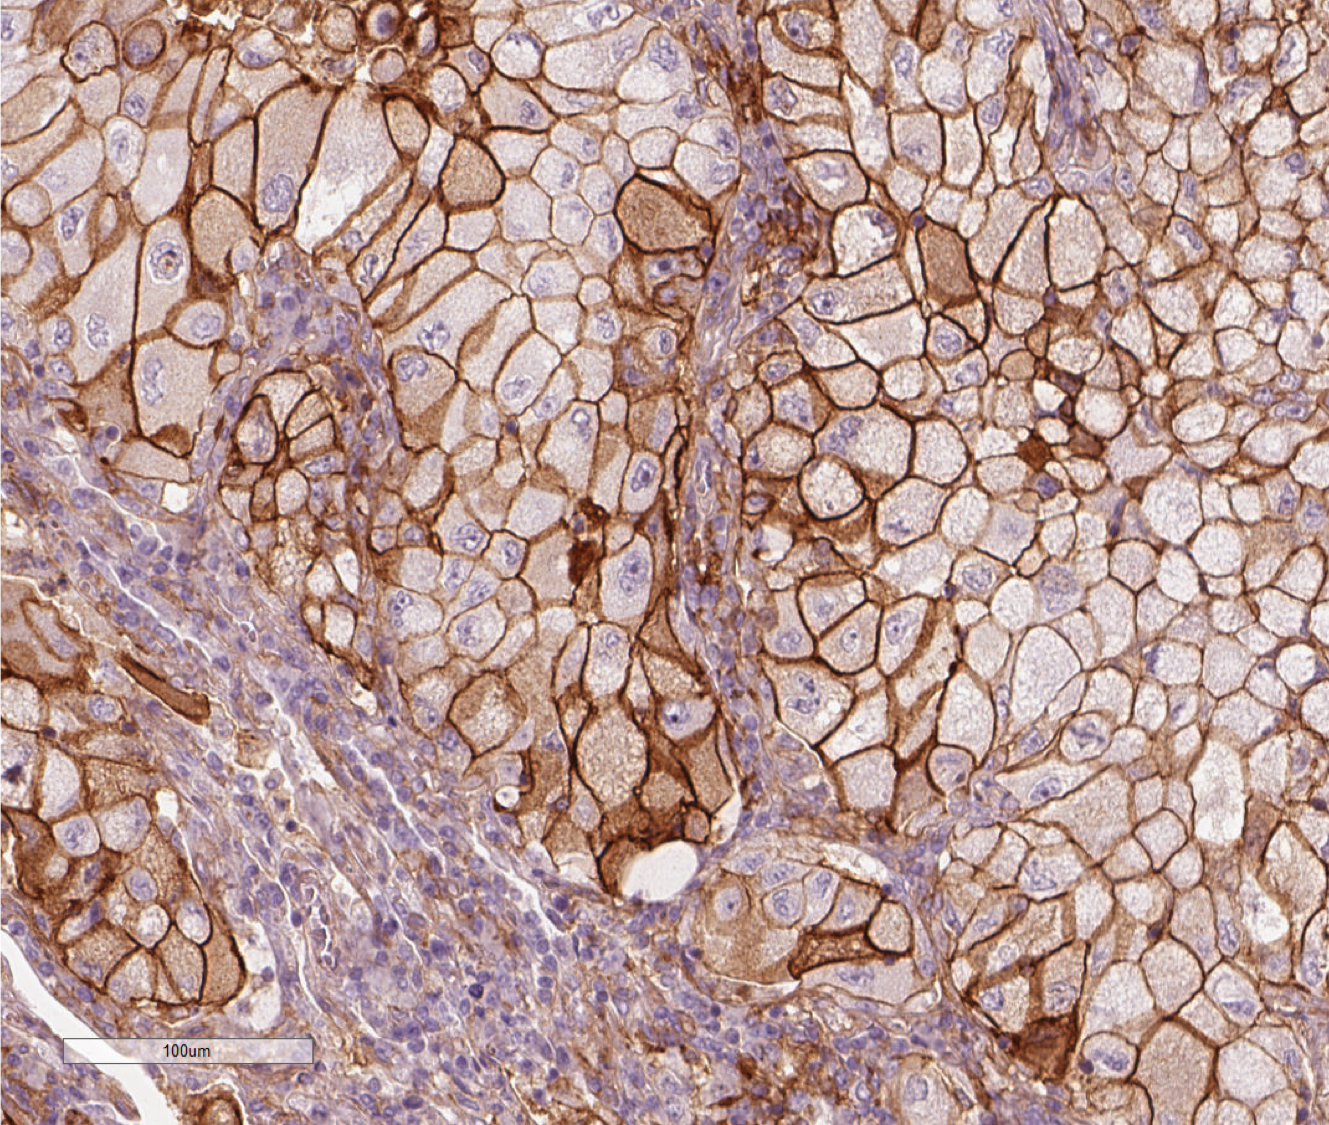

Bei Krebs kommen verschiedene Therapien zum Einsatz. Von besonderem Interesse ist die Krebsimmuntherapie, bei welcher von Krebszellen zunächst gehemmte Immunzellen wieder aktiviert werden. Für die Aufklärung der zugrunde liegenden Mechanismen haben James Allison und Tasuku Honjo 2018 den Nobelpreis für Medizin erhalten. Bei dieser innovativen Therapieform ist es wesentlich zu wissen, wie sich die Krebszellen gegen das Immunsystem zur Wehr setzen. Dazu nutzen Krebszellen beispielsweise das Molekül Programmed Death Ligand 1, kurz PD-L1. Mittels PD-L1 kann die Krebszelle Rezeptoren auf den Immunzellen blockieren und so die Zelle in einen Dornröschenschlaf versetzen. Dr. Karolina Edlund vom IfADo hat in einer aktuellen Studie grundlegende Beobachtungen gemacht, um den Einfluss des Immunsystems besser zu verstehen.

Ein sehr überraschendes Ergebnis war, dass sich zunächst kein Zusammenhang von PD-L1 mit der Überlebenszeit der Lungenkrebspatienten zeigte. Eigentlich hatten die Forschenden einen solchen Zusammenhang erwartet. Erst bei der Betrachtung von Krebszellen von Patienten, die noch nie geraucht hatten, zeigte sich ein signifikanter Zusammenhang mit PD-L1: Je mehr PD-L1, desto kürzer ist ihre Überlebenszeit. In Zukunft wird es also wichtig sein, bei der Planung von Therapiestudien die PD-L1 Ausschüttung des Tumors und das Rauchverhalten zu berücksichtigen.